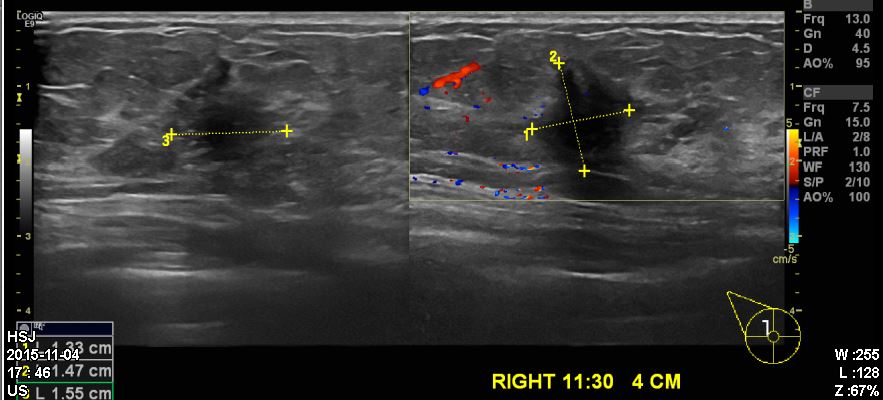

건진상 이상소견으로 내원하신 40대 환자분이십니다.

타원에서 진행한 유방초음파상 우측유방에 11시30분방향에 확인되는 혹을

조직검사시행하였고 침윤성유관암진단되었습니다.